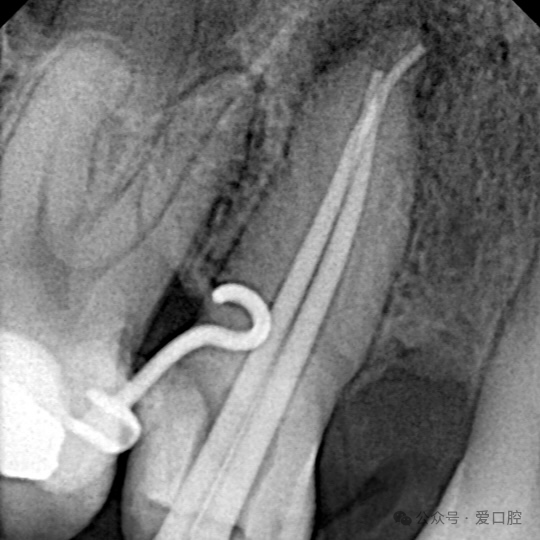

影像学检查:小牙片示:15冠部高密度影,根管内可见高密度影像,牙周膜增宽影,根尖低密度影。CBCT示:15遗漏腭侧根管。

15,安放橡皮障隔离后,显微镜下,开髓,暴露髓腔内牙胶,去除髓腔内牙胶,探查颊侧根管,使用再治疗镍钛锉去除根管上段牙胶,8号k锉,10号k锉疏通至根尖,3%次氯酸钠溶液冲洗,根测长度为19mm,3%次氯酸钠溶液冲洗,探查腭侧根管,发现髓室顶未揭干净,有牙胶残留,揭净髓室顶,去净残留牙胶,疏通腭侧根管至根尖,3%次氯酸钠溶液冲洗,根测长度为19mm,镍钛预备至3504,试尖, 3%次氯酸钠溶液冲洗, Eddy荡洗(20秒3次),蒸馏水冲洗,17%EDTA溶液冲洗,蒸馏水置换,吸干,氢氧化钙封药,玻璃离子暂封。